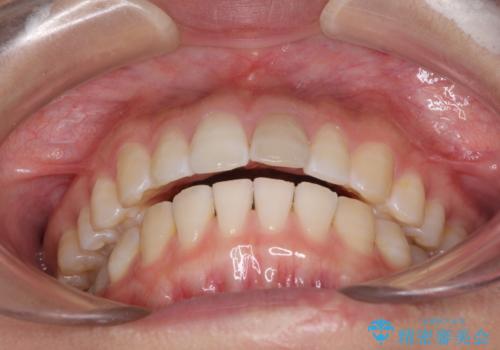

- 変色した前歯と突出した口元を気にして来院された患者様です。

口元の突出感はインビザラインにより歯列を整え、その後に、前歯をオーダーメイドタイプのオールセラミッククラウンにて補綴治療することとしました。

長時間のマウスピース装着と、患者様自身でのゴムかけに協力いただき、口元の突出感をしっかりと改善することができました。

前歯のオールセラミッククラウンもまるで本物の歯のように仕上がり、患者様には大変満足していただきました。